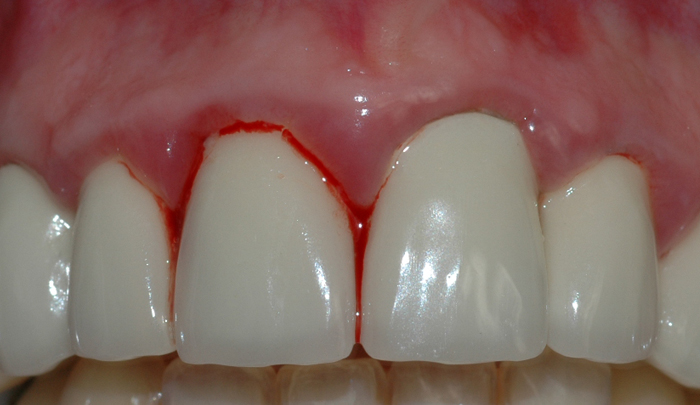

Et friskt tannkjøtt har lys rød farge og ligger stramt inntil tennene (fig. I). Et betent tannkjøtt får en mørkere rødfarge, det blir hovent og kan føles ømt ved berøring. Videre vil man kunne oppleve at tannkjøttet blør ved rengjøring og at det ligger mindre stramt inntil tennene.

Fig 1: Et friskt tannkjøtt har lys rød farge og ligger stramt inntil tennene Fig 2: Mangelfullt renhold kan over tid føre til utvikling av gingivitt